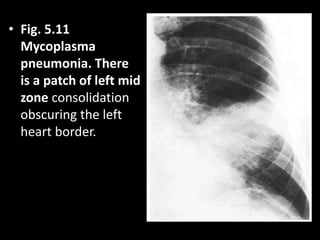

• Fig. 5.11

Mycoplasma

pneumonia. There

is a patch of left mid

zone consolidation

obscuring the left

heart border.

• Fig. 5.11 Mycoplasma pneumonia.There is a patch of left mid zone consolidation obscuring the left heart border.